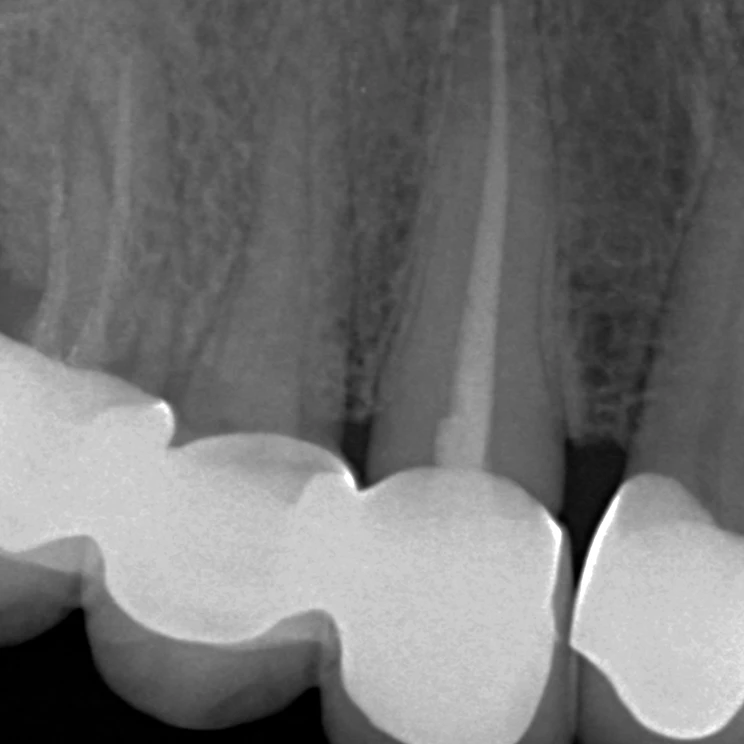

Wurzelspitzenresektion (WSR) –

Zahnerhalt durch chirurgische Präzision

Manchmal reicht eine klassische Wurzelkanalbehandlung nicht aus, um eine Entzündung dauerhaft zu beseitigen. In solchen Fällen kann eine Wurzelspitzenresektion (WSR) helfen, den betroffenen Zahn trotzdem zu erhalten.

Bei diesem chirurgischen Eingriff wird die entzündete Wurzelspitze sowie das umliegende entzündete Gewebe gezielt entfernt. Anschließend wird der Wurzelkanal dicht verschlossen, sodass sich die Entzündung nicht erneut ausbreiten kann.

Die Behandlung erfolgt schonend, präzise und unter modernen technischen Voraussetzungen. Ziel der Wurzelspitzenresektion ist es, den natürlichen Zahn zu erhalten und Schmerzen oder wiederkehrende Entzündungen nachhaltig zu beseitigen.

Dank sorgfältiger Planung und moderner Verfahren ist die WSR heute ein gut kalkulierbarer Eingriff mit hohen Erfolgsaussichten – für den langfristigen Erhalt Ihrer eigenen Zähne.